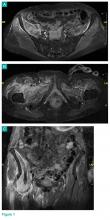

Figure 1.

Based on these findings, a magnetic resonance imaging (MRI) was ordered; representative images are shown (Figures 1a-1c).